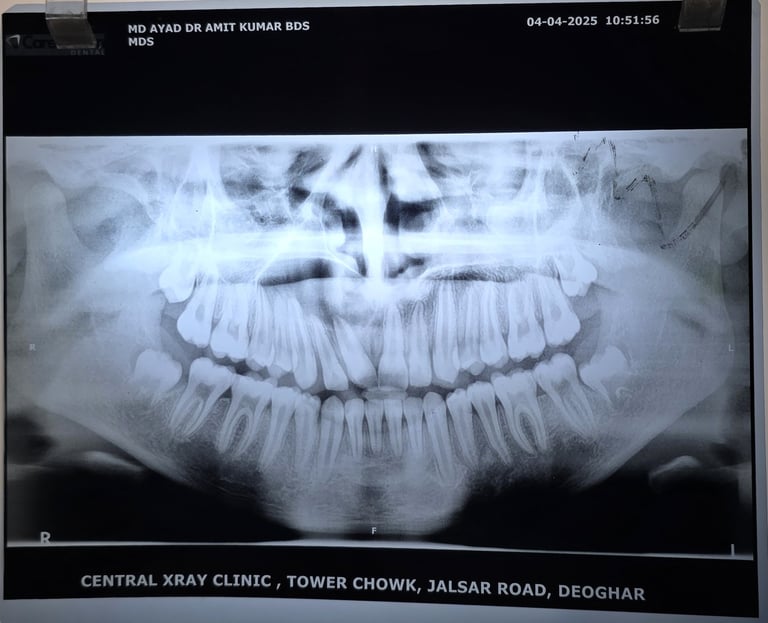

Radiographic Findings (Insert X-ray or CBCT):

Well-defined 4 cm radiolucent lesion extending from central incisor to premolar

Root resorption noted in adjacent teeth

📌 Alt Text: Large radicular cyst involving anterior maxilla in a 15-year-old